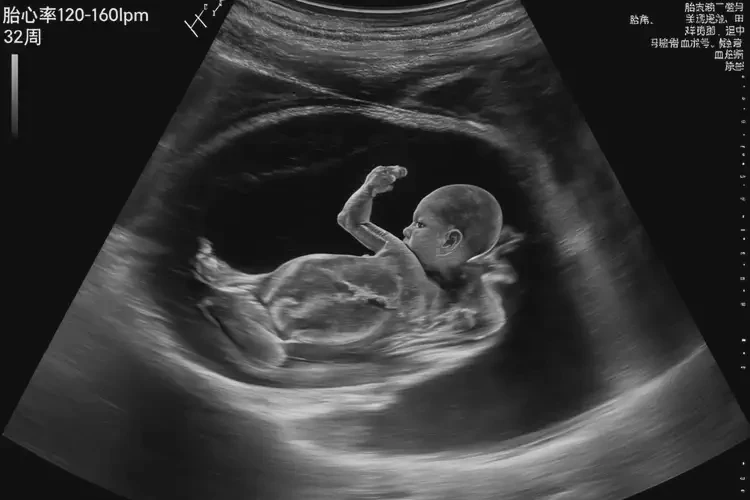

懷孕第32周胎心106正常嗎

胎心106次/分鐘在懷孕第32周不正常。

懷孕第32周時(shí),胎兒的正常胎心率范圍應(yīng)在120-160次/分鐘之間。胎心率低于120次/分鐘或高于160次/分鐘都可能表示胎兒存在健康問(wèn)題,需要進(jìn)一步檢查和評(píng)估。

29-32周120-160

從上表可以看出,在懷孕第32周時(shí),胎兒的正常心率范圍應(yīng)在120-160次/分鐘之間。